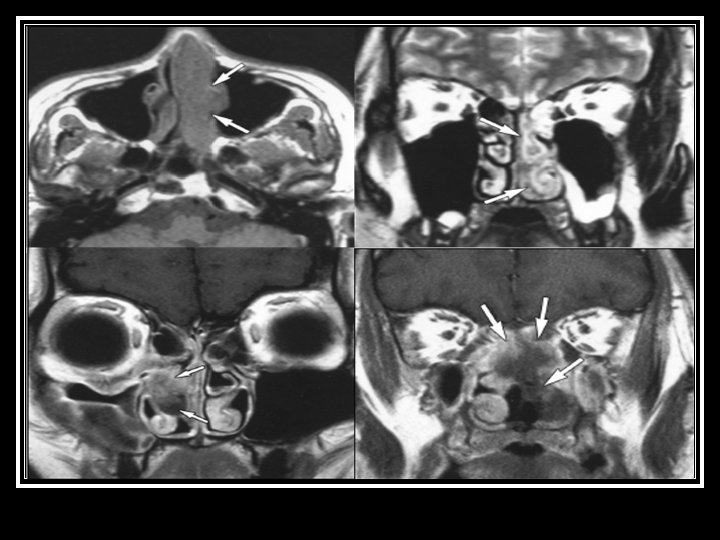

Private MRI Hyperintense spots in antero-superior part of lateral end of both IAM n Short hyperintense line in labyrinthine portion of right facial nerve n Suggestive of bilateral facial neuritis n MRA showed normal vasculature n Incidentally retention change over bilateral paranasal sinuses n

(4) Neurologist assessment: summary Initial presenting illness n Bulbar palsy with normal NCT, but clinically nil response to IVIG and steroid Deterioration right now n Cerebral dysfunction with raised CSF protein n Hypointensities in bilateral temporal and Rt BG Need to consider other diagnosis n Sinusitis with orbital + CNS extension n For contrast MRI brain + skull base

Searching for an answer, again…. . n n n n n 9 th July: Plain CT Brain (Hospital A) 7 th Aug: Plain CT Brain (Hospital A) 25 th August: Plain CT Orbit (Hospital A) 27 th August: Contrast CT brain + Sinus 4 th September: MRI brain + brainstem 4 th September: Plain CT brain 10 th September: Contrast CT brain 11 th September: Plain CT sinus 15 th September: MRI brain + DWI

Summary of progression • June/ 2010 n • July/ 2010 n • Early Aug/ 2010 n • Late Aug/ 2010 n • Sept/ 2010 n Lt face weak Bulbar palsy Dilated Rt pupil and uveitis Endophthalmitis and high fever Deep coma, tetraplegia, high fever n n n Nil imaging Facial neuritis Bilateral basal ganglia change Bilateral temporal + BG + thalami + pons